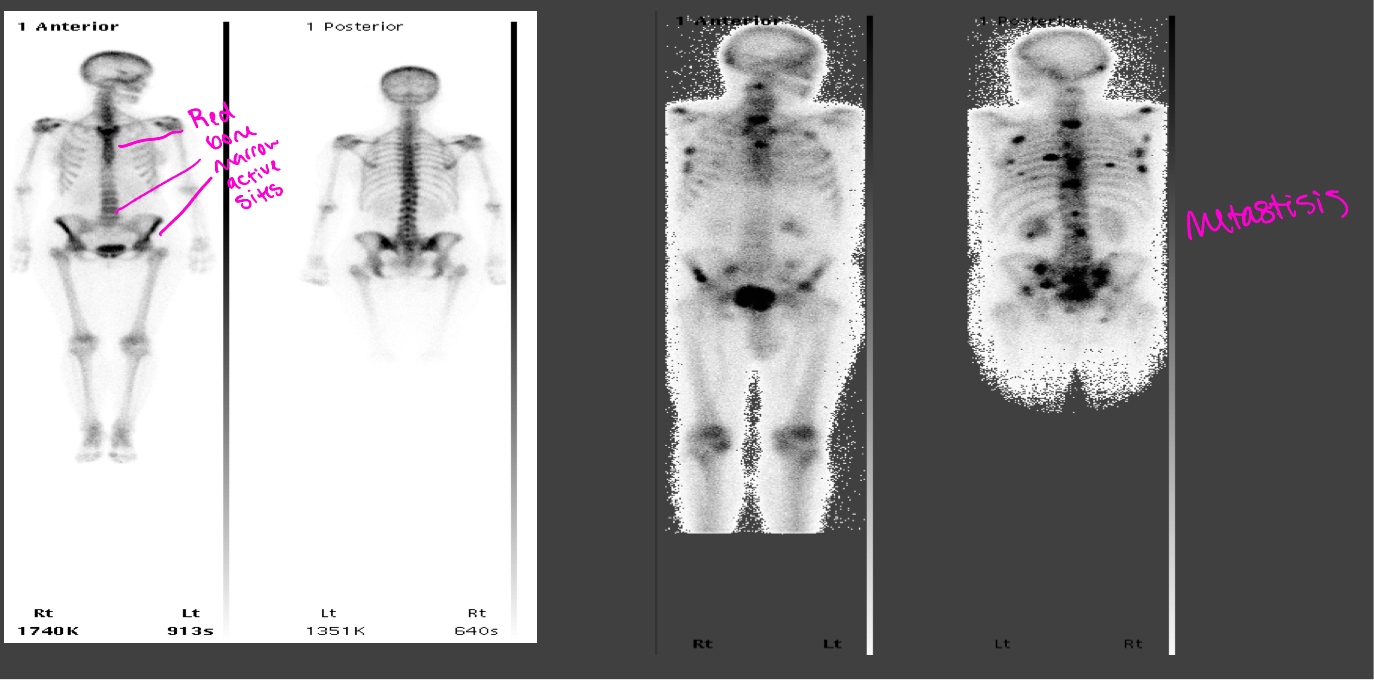

Common NM scan- Bone scans

99mTc-MDP- taken up in areas of osteoblastic activity and is used to evaluate bone pathology, CANCER (blast)

Normal bone scan vs abnormal bone scan with metastisis